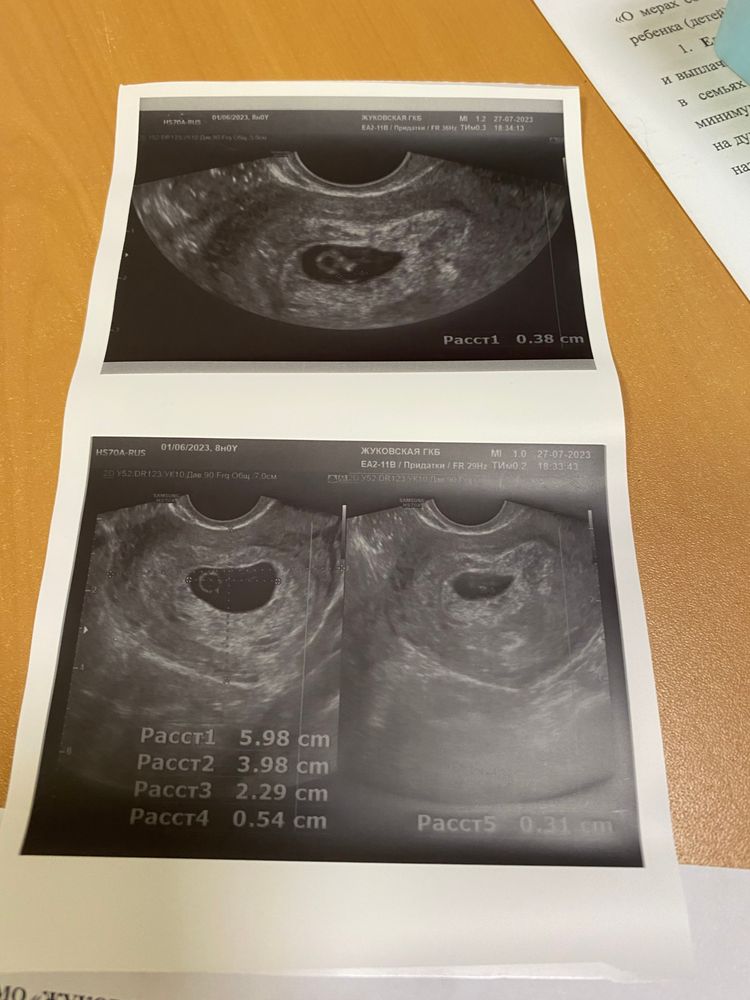

Определите срок

Изображение

Что скажите про УЗИ